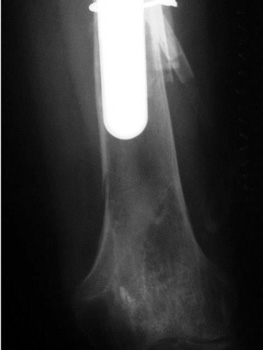

Insufficiency fracture lateral tibial plateau in patient with long revised left femoral stem